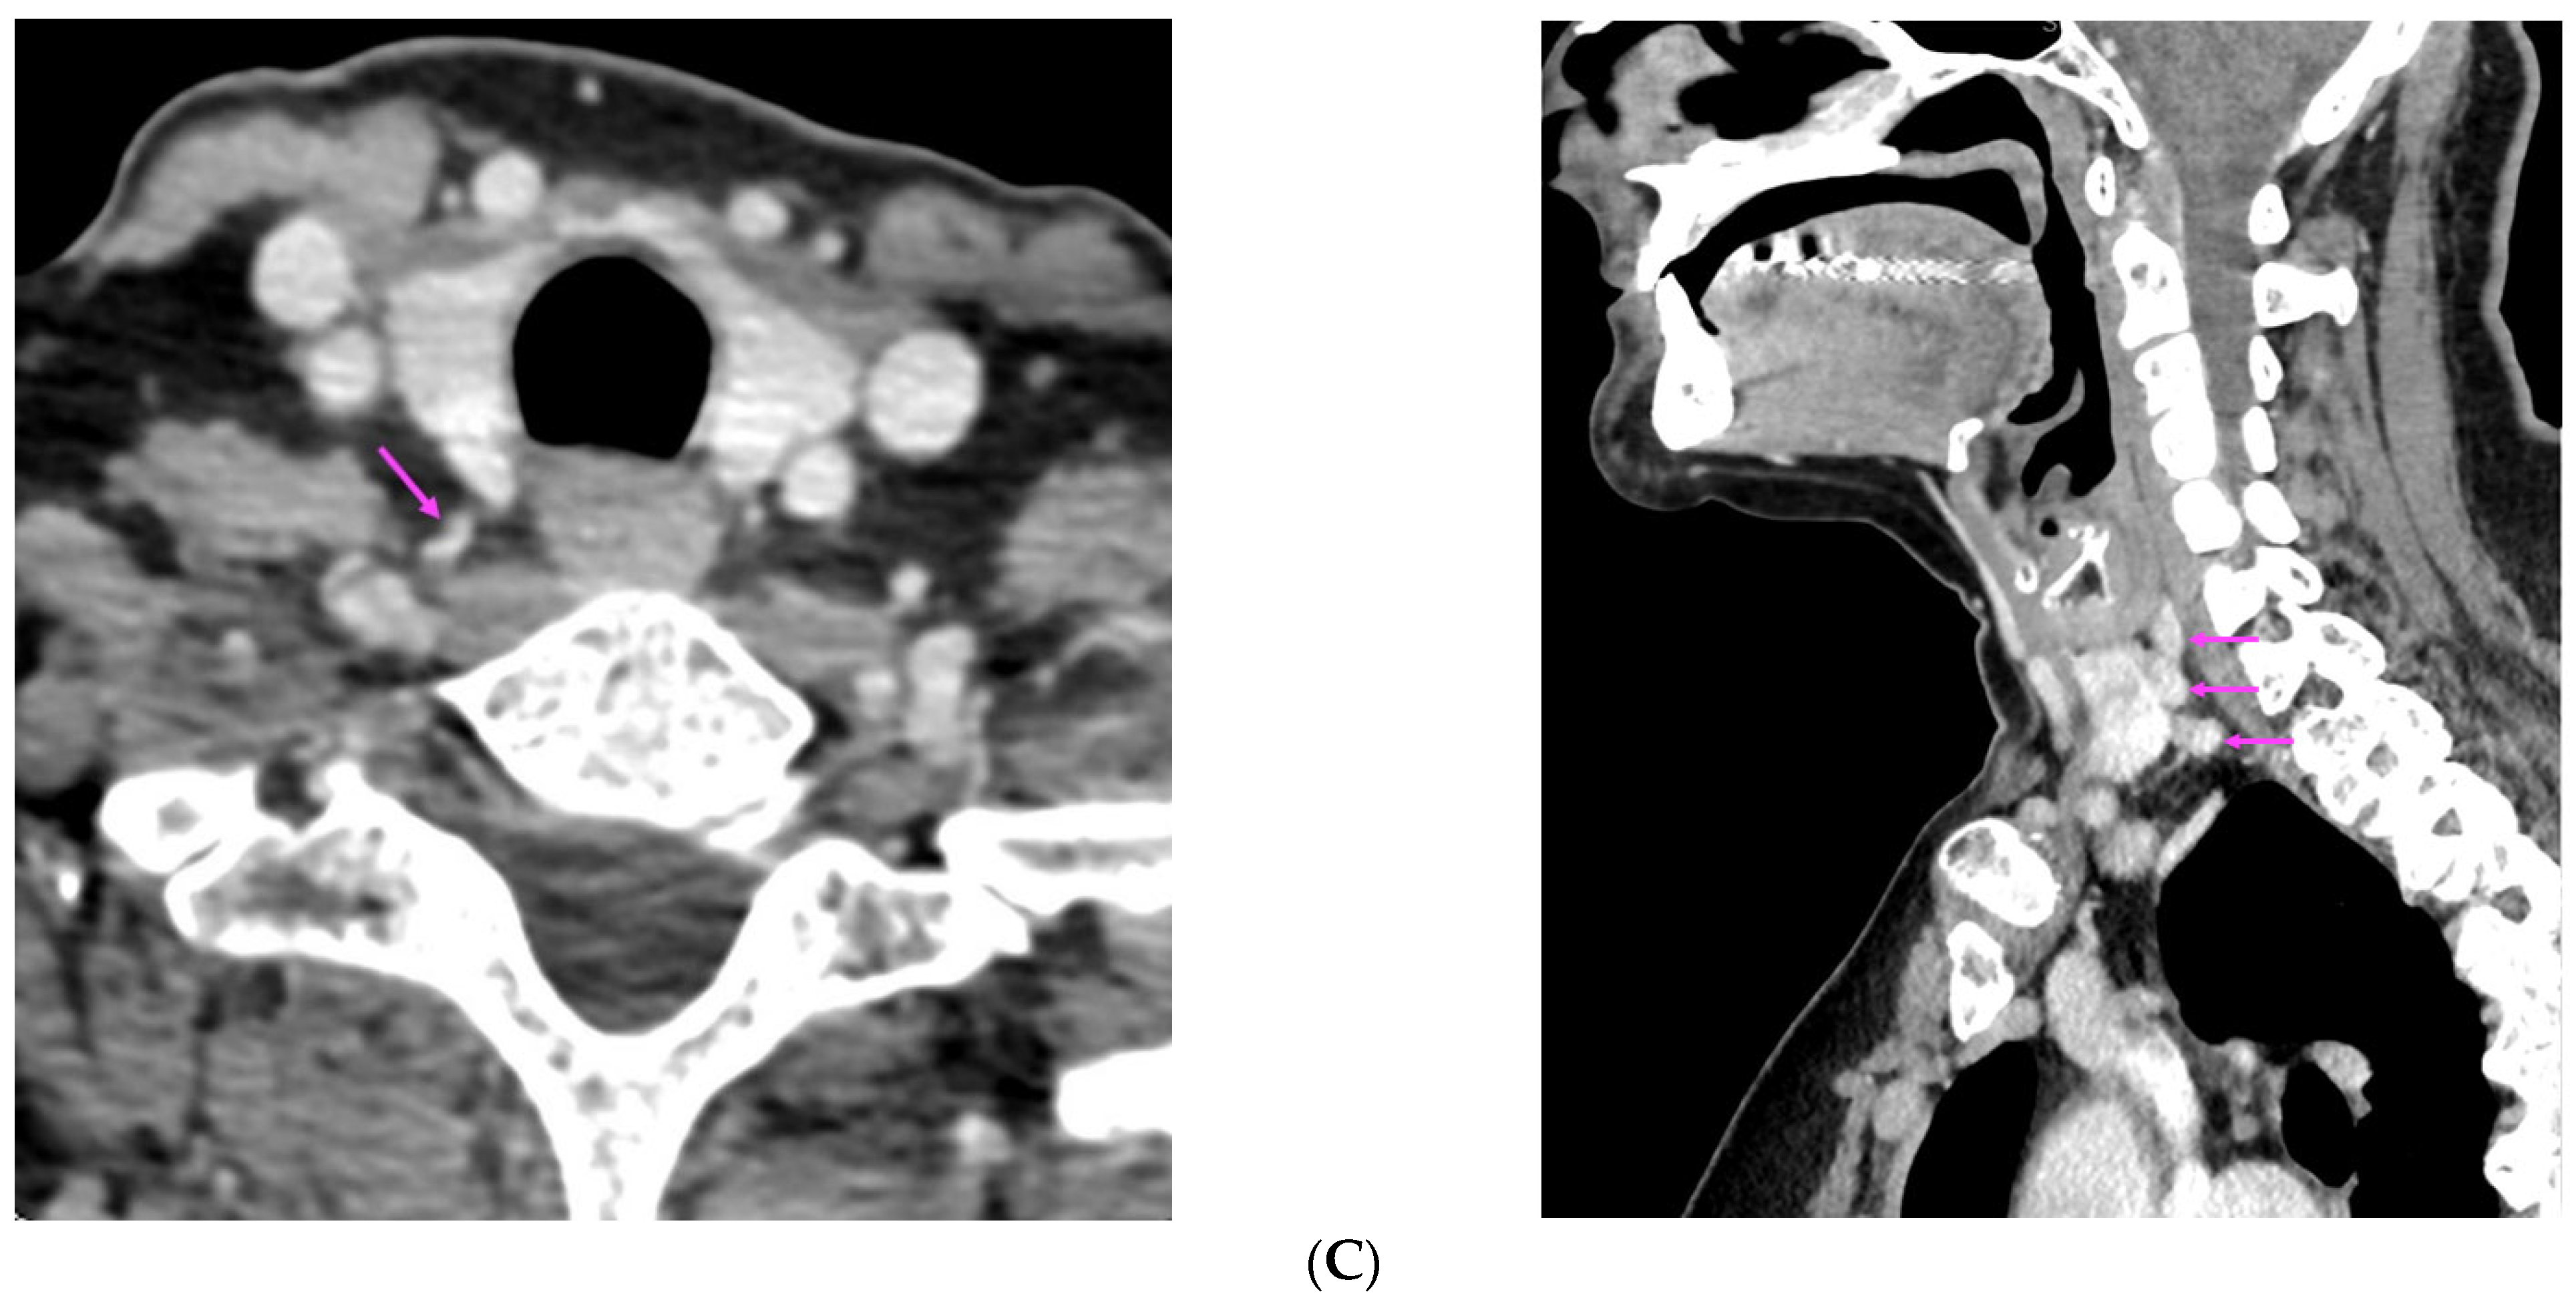

| [38] | 99m-Tc-MIBI imaging (SPECT/CT): three foci of elevated uptake on early phase with slow washout on delayed phase | Hyperplastic parathyroid tissues |